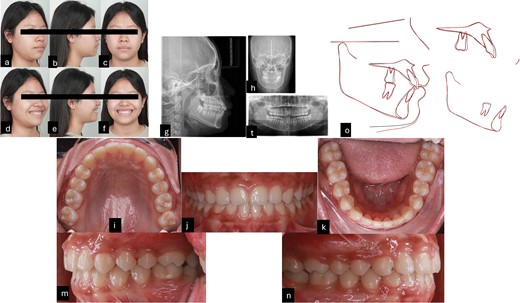

Intraorally, the patient is skeletal Class II with Class I molar, deep curve spee, anterior spacing upper and lower, abnormal position of the tongue and tongue posture, and short teeth were also noted. Extraorally, the patient had convex profile, proclined the upper incisors and GS but the upper lip of the patient was asymmetrical during smiling. The pre-treatment radiographies showed proclined upper incisors, deep curve spee, spacing, and four impacted wisdom teeth (Fig. 1).

Pre-treatment records. (a–f) Extra oral pictures; (g–t) pre-treatment radiographies; (l–n) intraoral pictures.